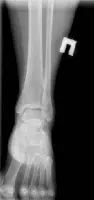

Стандартний рентгенографічний аналіз області гомілковостопного суглоба включає візуалізацію 2 видів: прямого заднього та бокового. У деяких випадках роблять знімок у косій проекції.

Прямий задній вигляд дозволяє оцінити стан суглобової щілини, яка має ширину 3-4 мм. Також на знімку можна розглянути кісточку, таранну та гомілкові кістки. Щоб досліджувати їх детальніше, використовується коса проекція.

Бічний вигляд дозволяє виявити переломи, вивихи та суглобові випоти навколо гомілкостопа. Крім того, проекція допомагає в оцінці тяжкості травм кістки п’яти шляхом вимірювання кутів Беллера і Гиссана, які в нормі рівні 20-40° і 94-136° відповідно.

При розгляді рентгенограм вивчаються м’які тканини на наявність набряку. Скупчення рідини в області зчленування латеральної та медіальної кісточок є ознакою переломів та травм зв’язок. Випіт може бути ідентифікований за наявності ущільнень тканин спереду та ззаду суглоба.

На знімках погано видно зв’язки та сухожилля, проте добре проглядається ахілове сухожилля. Його нормальний діаметр у середньому становить 6 мм. Значення параметра понад 8 мм вказує на патологію сухожиль, причиною може бути дистрофічне ураження найближчих м’язів, розрив, запальні артропатії, післяопераційні зміни.